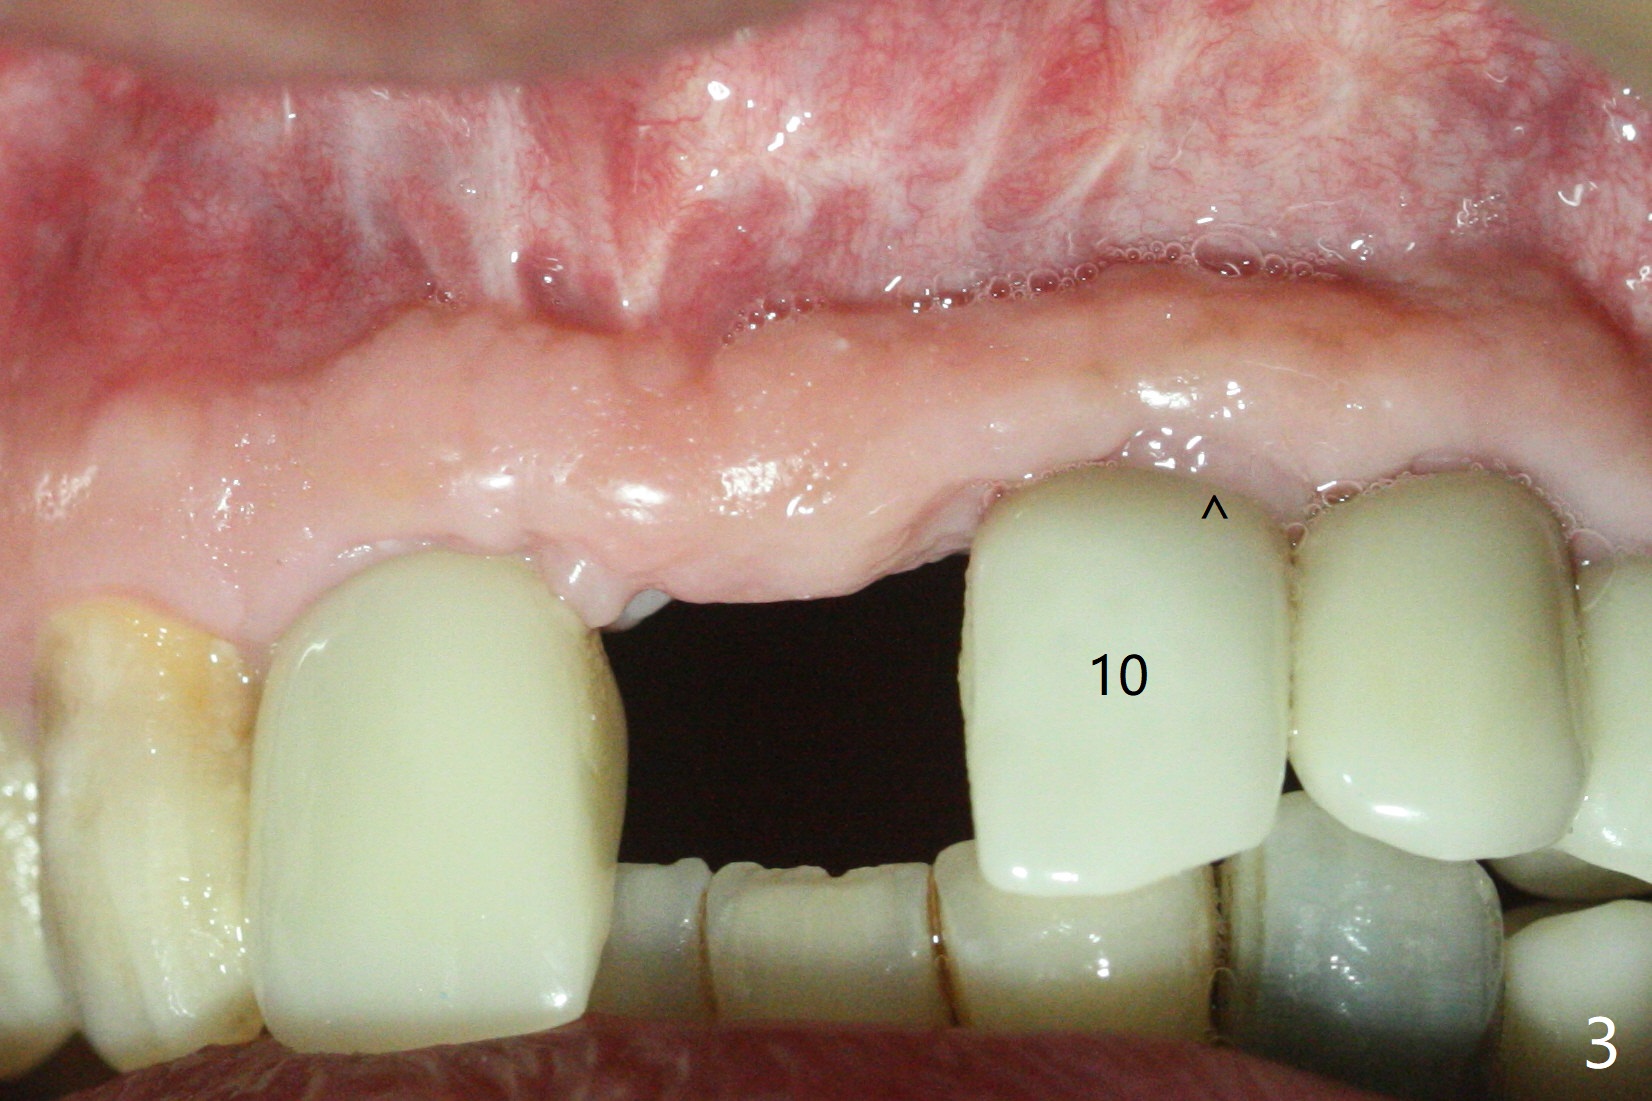

The implant access at #9 closes 1 week post implant fracture (Fig.1,4). There is mild gingival erythema at #10 (Fig.2,3 ^). There is bone around the fractured implant, which is palatally placed (Fig.5). The 2 mm implant is removed using 2/3 mm trephine bur. In spite of moving the osteotomy buccally, a 4.5x4 mm, 15 degree A-type angled abutment is installed for an immediate provisional following placement of a 3.5x10 mm implant (Fig.7, 25 Ncm). Sticky bone is placed (Fig.7 *) palatal to the implants at #9 and 10 (with thread exposure, Fig.6). While the majority of periodontal dressing remains in place (Fig.9,10), the suture in the exposed area appears to hold the papilla in place (Fig.8 <). Herpetic infection develops in the palate (Fig.9). Two months later, the gingiva at #10 is healthy; it appears that the implant threads are covered by bone graft. The immediate provisional (fabricated before suture) keeps the gingiva in an ideal position for impression of final restoration. It appears that the access hole is in a right area for screw retained restoration. The gingival cuff is healthy immediate pre-cementation, 4 months postop (Fig.12,13). The lab does not make access hole for the final crown (Fig.14). The implant remains subcrestal 4 months postop (Fig.15). Since the shade of the crown is off, the abutment remains un-torqued and the crown is cemented with temp bond. The implant threads at #10 seem to be covered by bone graft 4 months postop (Fig.16).